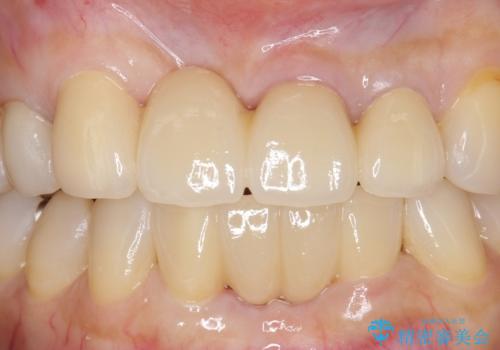

抜歯後、骨と歯肉の回復を待ち、オールセラミッククラウンによるブリッジで補綴を行いました。

今回用いたオールセラミッククラウンはジルコニアフレームという白い素材の上にセラミックを盛っているため、審美性が非常に高いのが特徴です。

また、ジルコニアは人工ダイヤモンドの材料にも使われているほど高い強度を持っており、そのためオールセラミッククラウンは審美性だけでなく、奥歯やブリッジの補綴も可能とするクラウンです。